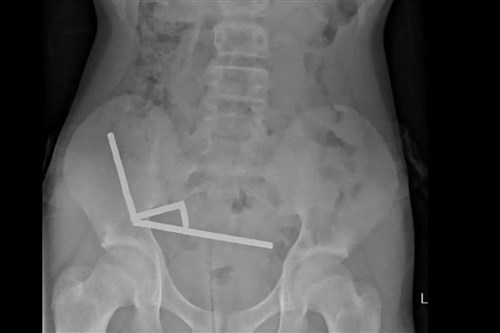

Mivel a világ legerősebb mágnestípusa, a neodímium 2013 óta be van tiltva Új-Zélandon, a 13 éves fiú a Temuról rendelte meg száz darabot. Meg is érkeztek az 5x2 milliméteres kis mágnesek, amelyeket a fiú valamiért lenyelt. Ez nem volt jó ötlet, ugyanis a mágnesek – meglepetés! – egymáshoz tapadtak odabenn, négy egyenes vonalban felsorakozva a gyermek belében.

Nem tudni, mire gondolt a költő (kép: New Zealand Medical Journal)

Négy nap hasi görcs után a fiút a North Island-i Tauranga Kórházba szállították, ahol megműtötték. Az orvosok szerint a mágnesek nyomása négy területen a szövetek elhalását, vagyis nekrózist okozott a vékonybélben és a vakbélben. A sebészek eltávolították az elhalt szöveteket és kivették a mágneseket, majd a gyermek nyolcnapos kórházi kezelés után hazatérhetett.